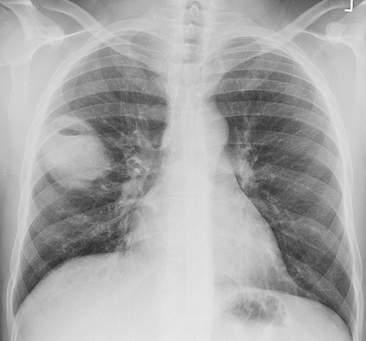

Hình ghi lại được càng đen nếu có càng nhiều tia X được chiếu đến phim. Vì vậy những bộ phận cơ thể cản nhiều tia X thì sẽ cho hình trắng, trong khi những bộ phận cơ thể rỗng hoặc đầy khí như phổi thì sẽ cho hình đen. Hình ảnh ghi lại được tại các mô mềm như cơ hoặc các tạng đặc trong cơ thể sẽ có màu xám, độ xám phụ thuộc vào đậm độ của chúng.